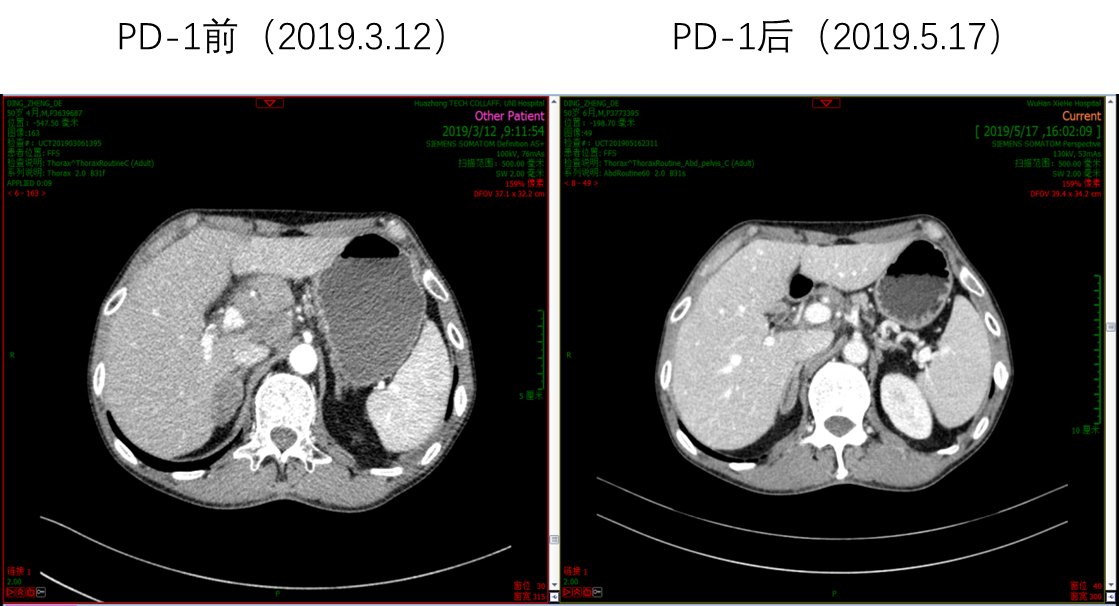

因患者PS评分差,故推荐单药PD-1单抗治疗,患者考虑后选择信迪利单抗。2019年3月20日开始使用信迪利单抗治疗1次,当日出现发热39.3℃,予以退热栓退热治疗后好转。4天后,患者PS评分明显好转,下床活动自如,食欲增强,PS评分由3分改善到1分。2019年4月11日和2019年5月1日分别再使用信迪利单抗治疗各1次。2019年5月17日复查腹部CT,肝脏病灶较前明显缩小,肝门淋巴结较前明显缩小;复查胸部CT,肺部病灶也较前明显缩小。总体疗效评价为PR。多次治疗中外周血EBV-DNA拷贝数检测结果显示,信迪利单抗治疗后EBV-DNA明显降低。

image017.png

图5  信迪利单抗治疗前后肝门淋巴结明显缩小